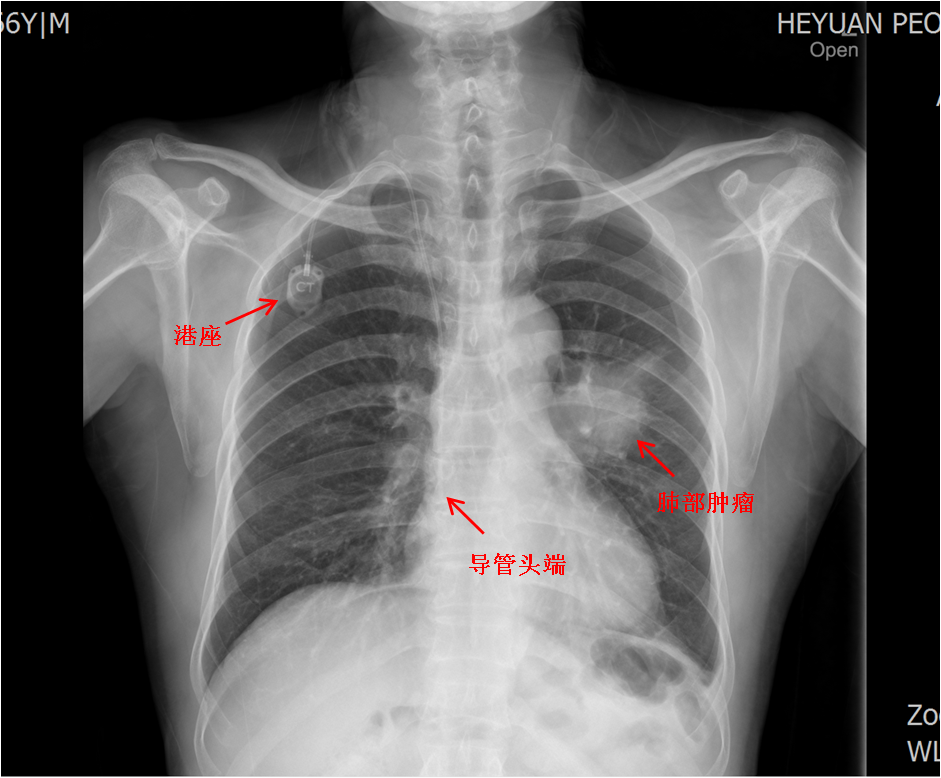

患者李某,增强CT扫描提示“左肺上叶中央型肺癌,侵犯左侧斜裂胸膜,伴左肺门多发淋巴结转移”,罗少华主任带领科室团队为患者行CT引导下经皮肺穿刺活检术,根据病理结果确诊为“左肺上叶鳞状细胞癌IV期”,制订治疗方案为化疗联合免疫治疗。因为需要行多周期化疗,且化疗药物输液外渗可能导致严重后果,所以化疗一般采取输液港植入或PICC置管。经知情同意,罗少华主任在手术室为患者行输液港植入术,术后第二天顺利行化疗+免疫治疗。

输液港植入术后常规行胸片检查,确认港座及导管头端位置

输液港,对应英文简称为Port,全称为“完全植入式静脉通路系统”,是完全植入人体内的闭合输液装置,可为患者提供长期的静脉血管通道。很多肿瘤病人及家属对输液港并不陌生,肿瘤患者由于病程长,治疗方案多,需反复接受化疗、营养支持等治疗,传统的输液方法通过外周表浅静脉穿刺注射液体,易引起浅静脉炎、药液渗漏、局部硬肿,甚至大面积组织坏死等并发症,给患者造成了很大的痛苦。而植入输液港就能很好地解决上述问题,如今输液港在各级医院越来越普及,尤其适合长期化疗、反复抽血、输血及需要长期静脉营养的恶性肿瘤患者,因此也被称为“化疗神器”。另外,关于置管深度问题,理想的导管头端应位于上腔静脉下段与右心房交界处,通常,呼吸科患者的深度较其他专科患者略深,因为前者容易咳嗽,剧烈咳嗽导致胸腔压力升高,导管有可能折叠或逆向漂移到颈内静脉,此时,输液港在调整前不宜使用。